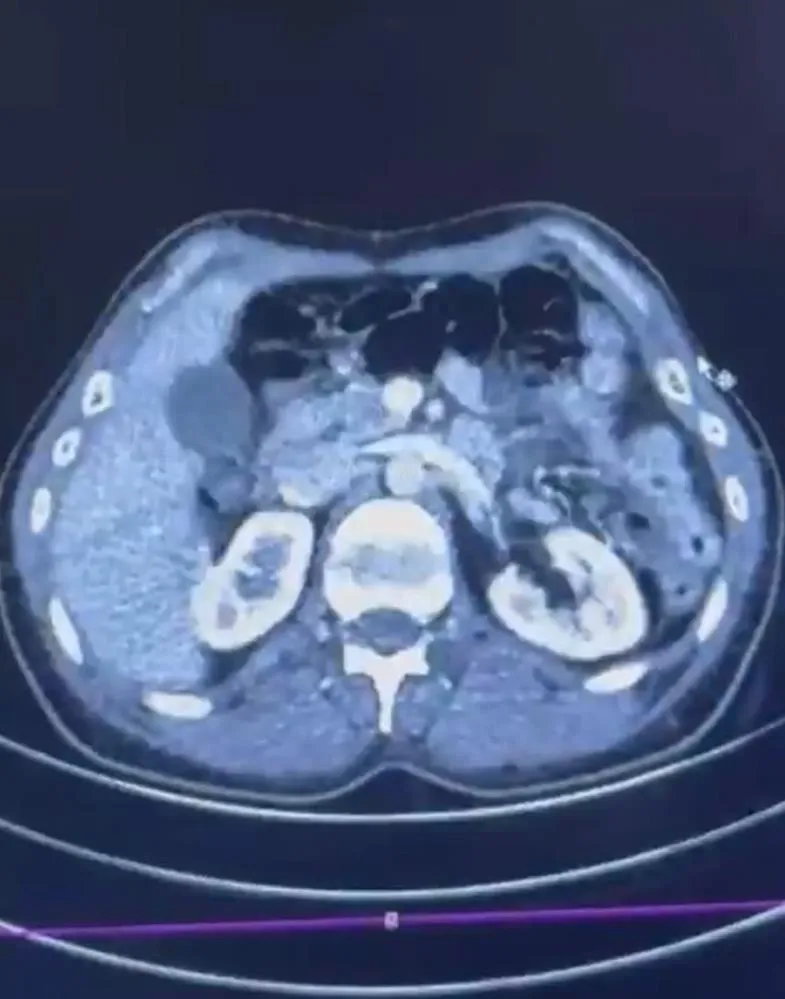

Düzenlenen operasyonda; S.C., R.B.C. ve G.M. yakalandı. S.C. ve R.B.C.'nin Kayseri Şehir Hastanesi'nde yapılan iç beden muayenelerinde, mide kısımlarında bulunduğu tespit edilen 50 adet kapsül şeklinde toplam 554 gram uyuşturucu madde ele geçirildi.